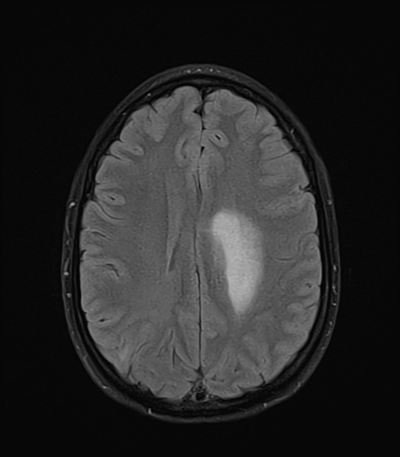

An 50 year-old man with lung adenoCA (known metastases to brain, spine, and adrenal glands) presents to the ED with worsening right arm and leg weakness. He had just gotten a routine MRI of his brain yesterday that re-demonstrated his known right occipital and left frontal metastases, though with an increase in vasogenic edema (mainly associated with the left frontal metastasis) as compared with prior. The ED consults you because of his abnormal MRI with worsening symptoms, and to inquire whether surgical intervention is acutely warranted.

MRI brain (FLAIR)

This patient has known metastatic lung cancer with two brain metastases. The vasogenic edema is noted to have increased from prior. Now he's having very rhythmic right arm jerking movements. Probably a focal seizure. What now though? It really depends on what is the patient's mentation. Let's say that in this case, he maintains awareness and is able to continue interacting with you quite well. That's encouraging. Since most focal seizures will end spontaneously after a few minutes, and because his mental status is reassuring, you choose to hold off on treatment. But, you do notify his ED nurse and the ED resident, in case treatment needs to be escalated.